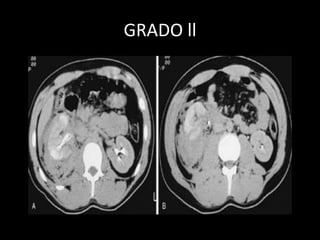

GRADO ll

TAC S-95 YE-97 •